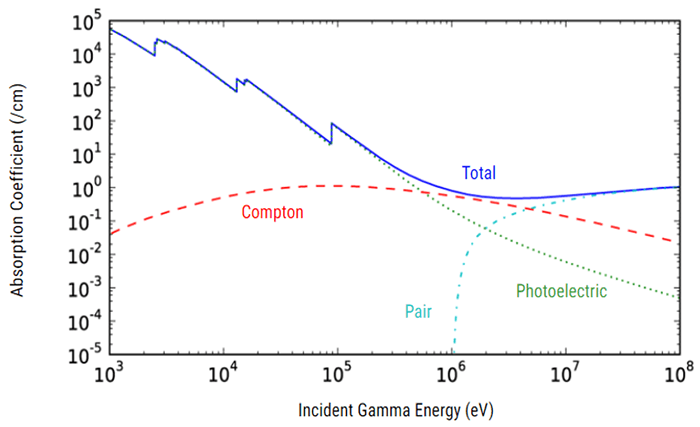

Attenuation is one of the physical principles of radiation interaction. If you recall, it is the reduction in the number of x-ray photons in the beam, and the subsequent loss of energy as the beam passes through the matter (or patient in this instance). In CT, as in diagnostic radiology, the attenuation is dependent on the type of tissue being scanned, such as the soft tissue, the bone, the blood or the muscle. Each type of tissue attenuates a different amount of photons which results in image differences on the finished scan. The denser the tissue, the more the attenuation of the beam.

It is important to know that X-ray penetration is an exponentially decreasing function of patient thickness. Thus, large patients will need a much larger dose. We use higher kVp to penetrate large people, large bony people, and bone. As we increase kVp, more of the beam penetrates the tissue with higher energy so they interact more by the Compton effect. This produces more scatter radiation which increases image noise, reduces contrast and increases the dose.

The type of interactions that occur between the patient’s body and the x-ray photons is a function of the selected kVp. Increasing the kVp will improve the signal-to-noise ratio. But decreasing the kVp will reduce the patient dose especially in pediatric and small adults. For contrast resolution of the gray-white matter (or soft tissue) in the brain, the high technique is necessary. Imaging in large patients can be improved also by using the maximum kVp along with an increase in scan time.